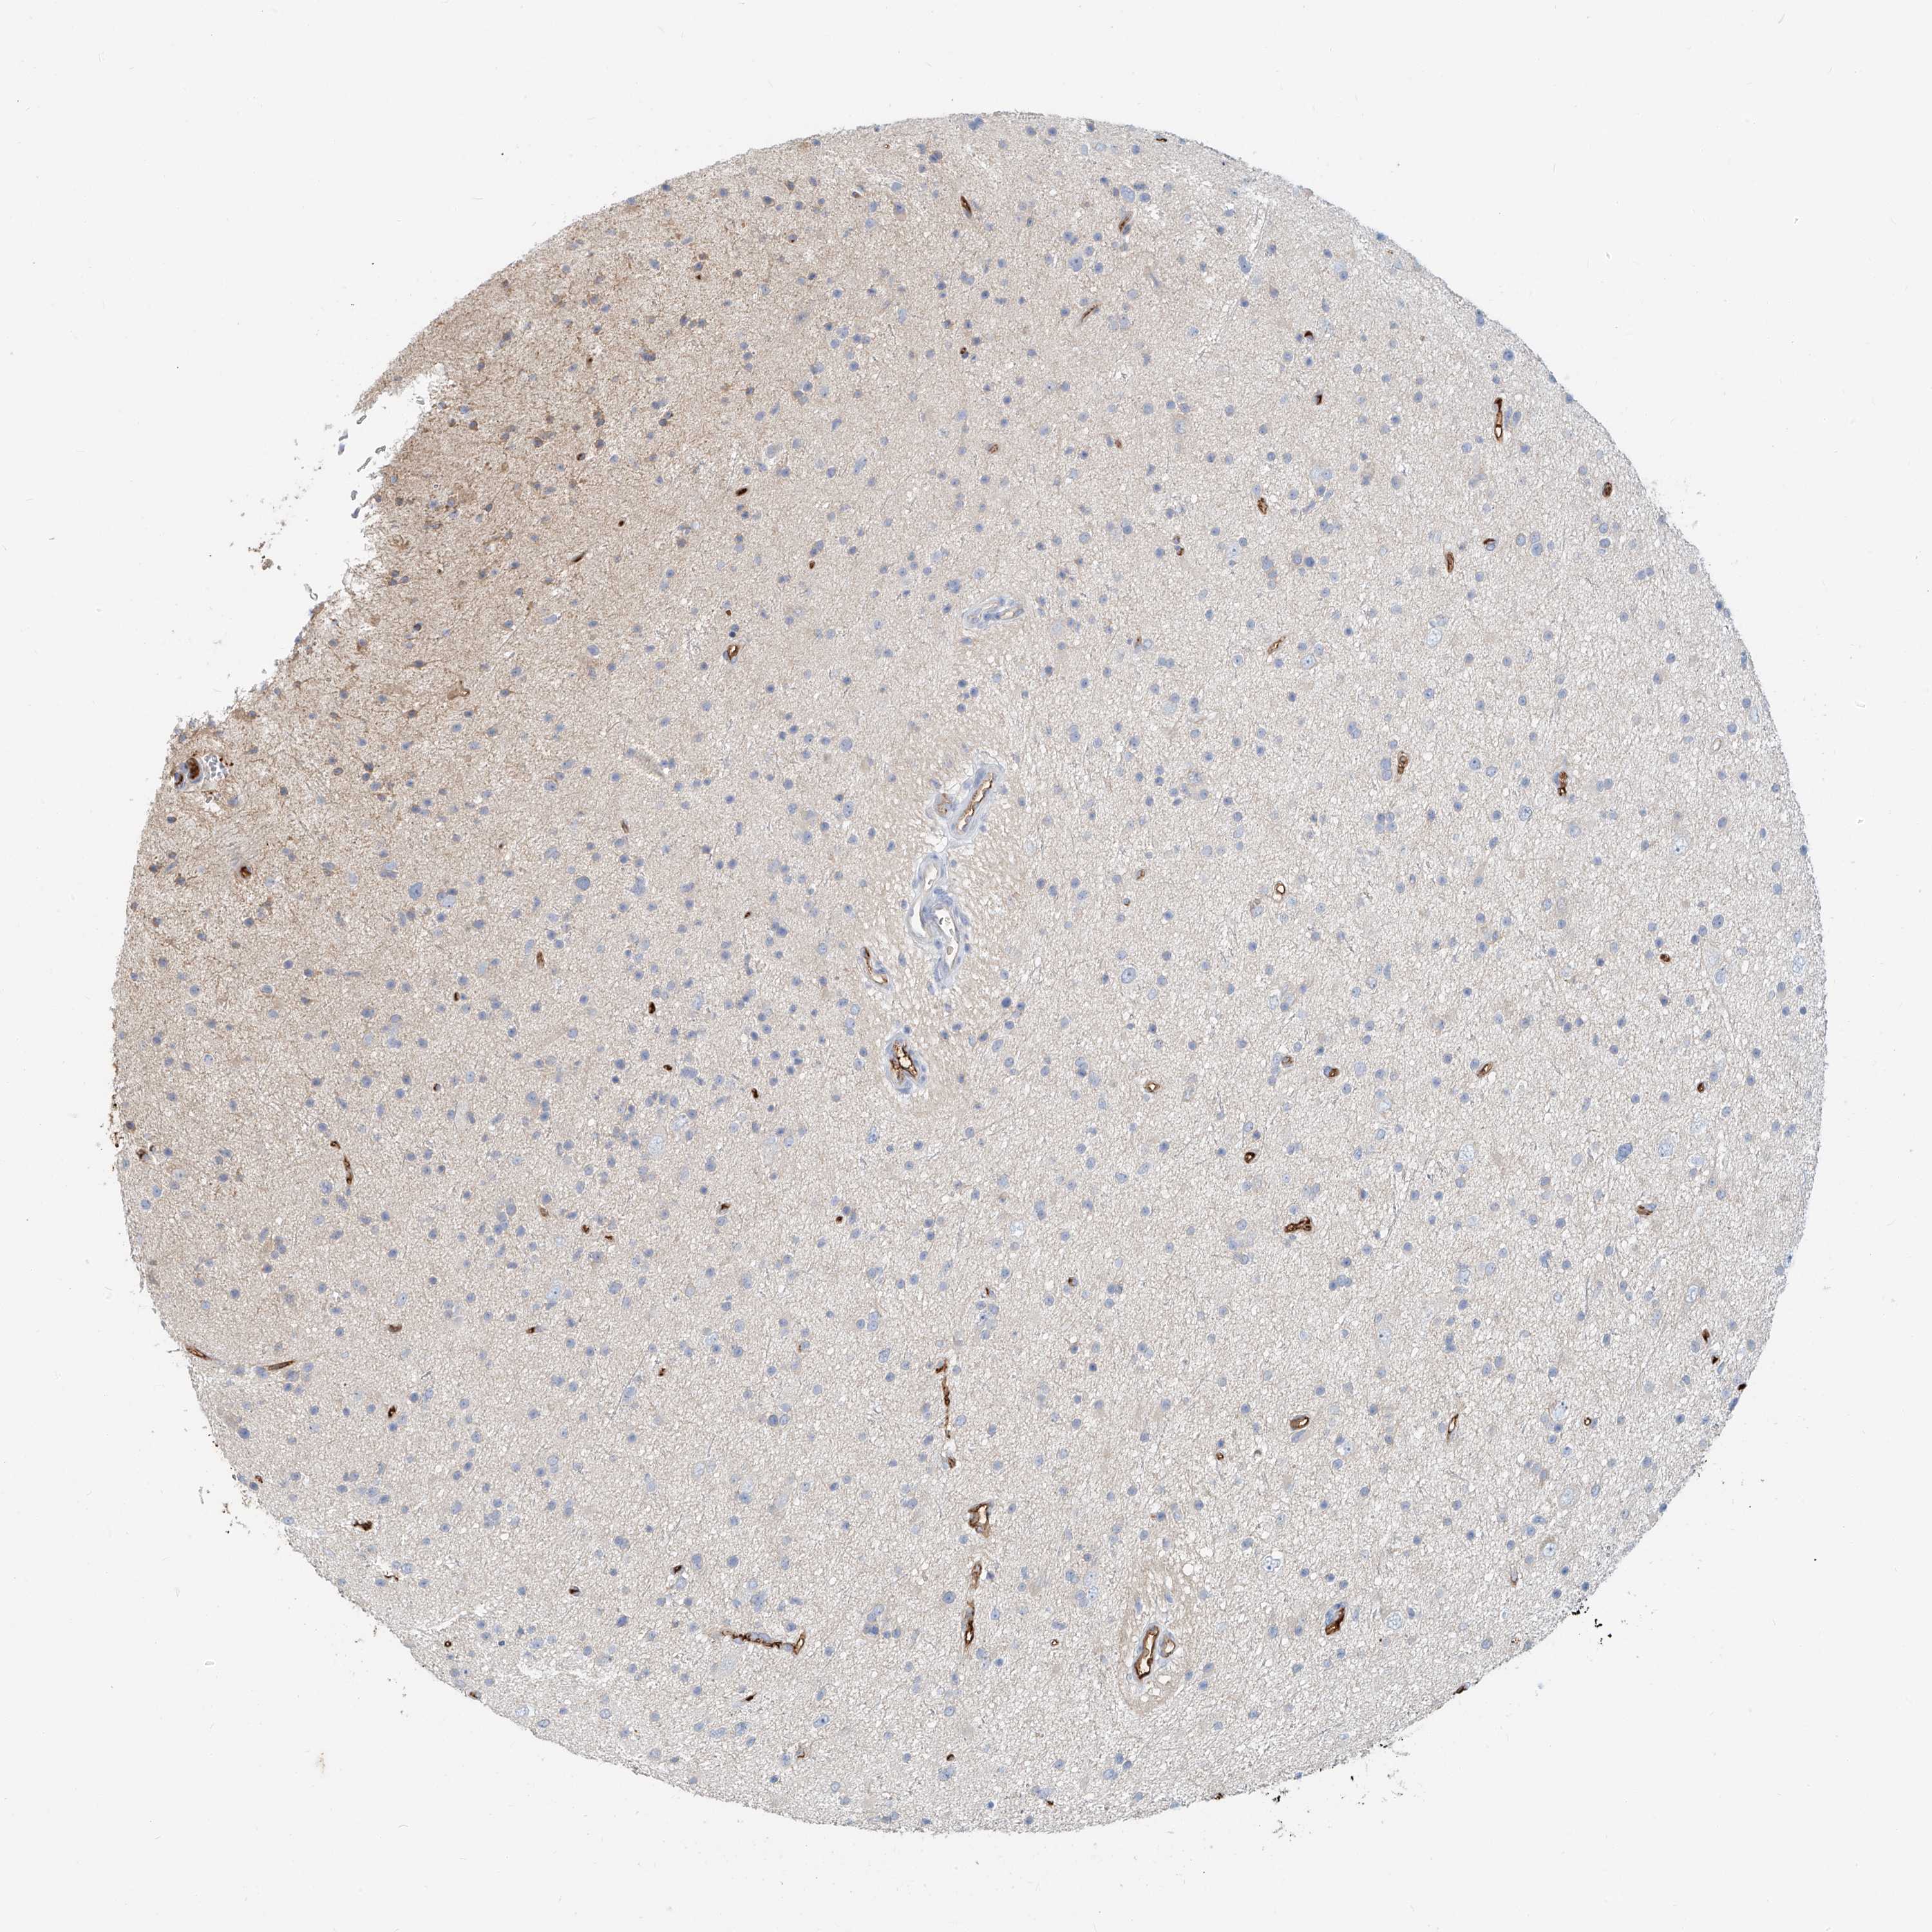

GLIOMA - Protein expressioni

A mouse-over function shows sample information and annotation data. Click on an image to view it in a full screen mode. Samples can be filtered based on level of antibody staining by selecting one or several of the following categories: high, medium, low and not detected. The assay and annotation is described here.

Note that samples used for immunohistochemistry by the Human Protein Atlas do not correspond to samples in the TCGA dataset.

Antibody stainingi

Antibody staining in the annotated cell types in the current human tissue is reported as not detected, low, medium, or high, based on conventional immunohistochemistry profiling in selected tissues. This score is based on the combination of the staining intensity and fraction of stained cells.

Each image is clickable and will lead to virtual microscopy that enables deeper exploration of all samples and also displays staining intensity scores, fraction scores and subcellular localization as well as patient and tissue information for each sample.

Antibody HPA030606

Staining

High

Medium

Low

Not detected

Intensity

Strong

Moderate

Weak

Negative

Quantity

>75%

75%-25%

<25%

None

Location

Nuclear

Cytoplasmic/membranous

Cytoplasmic/membranous,nuclear

Glioma, malignant, High grade

Glioma, malignant, Low grade

Glioblastoma, NOS